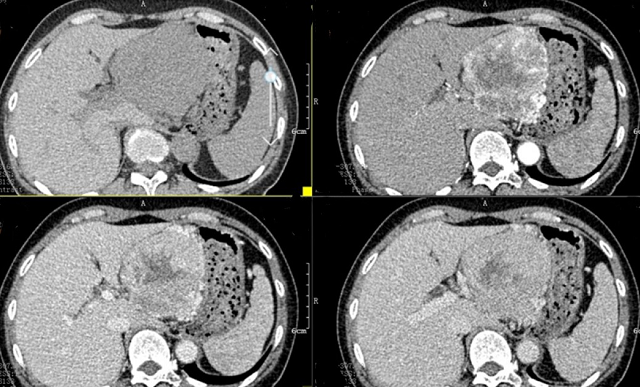

上腹部CT顯示胰腺巨大腫瘤

入院后,根據(jù)王女士病情,曹利平教授及其團(tuán)隊(duì)為她制定一套詳盡的術(shù)前檢查和治療方案。首先,安排做上腹部增強(qiáng)CT,并建議其先穿刺活檢明確病理。

“CT表現(xiàn)符合胰腺神經(jīng)內(nèi)分泌腫瘤,穿刺也證實(shí)無(wú)誤,但是瘤體實(shí)在太大,直徑約12cm左右,腹腔內(nèi)的門靜脈、腸系膜上靜脈、脾靜脈以及腹腔干這些重要血管統(tǒng)統(tǒng)包繞進(jìn)去了,且與周圍結(jié)腸系膜也有累及!

曹利平教授帶著團(tuán)隊(duì)成員逐一分析,隱藏在瘤體附近的血管就像埋在炸彈旁的導(dǎo)火索,稍有不慎,便會(huì)引爆這顆瘤體炸彈,要想把腫瘤完整切除,更是難上加難。